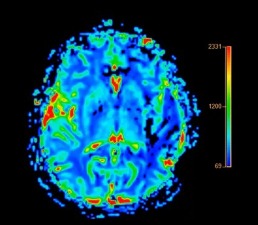

Des scientifiques découvrent un "complexe de mort" caché qui pourrait être à l'origine de la maladie d'Alzheimer